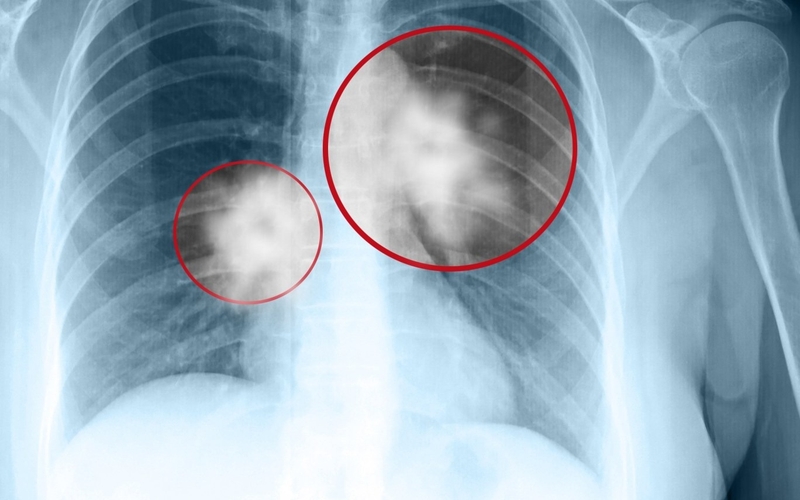

Vết mờ phổi lành tính có đặc điểm như: Nốt mờ hình tròn, có bờ đều, đường kính nhỏ hơn 3cm, nốt mờ không phát triển kích thước ít nhất trong vòng 2 năm. Mặt khác, vết mờ phổi lành tính có thể xuất hiện nốt vôi hóa có hình bỏng ngô, xếp theo tầng tại trung tâm, chiếm khoảng 10% thể tích nốt mờ. Vết mờ phổi lành tính thường gặp ở người dưới 35 tuổi, sinh hoạt và làm việc lành mạnh, không hút thuốc. Vết mờ phổi lành tính thường gặp và không nguy hiểm, tuy nhiên vẫn cần theo dõi định kỳ 3 - 6 tháng để đảm bảo vết mờ phổi không phát triển lớn hơn hoặc xuất hiện vết mờ mới.

Vết mờ phổi ác tính do ung thư thường có những đặc điểm như: Có đường kính trên 3cm, bờ không đều, có thể có vôi hóa, đặc biệt trong một khoảng thời gian ngắn kích thước và số lượng vết mờ tăng nhanh. Vết mờ phổi ác tính cần được kiểm tra bằng các xét nghiệm chẩn đoán khác, đặc biệt là sinh thiết để chắc chắn kết quả.

Hình thái vết mờ phổi do xơ phổi thường có dạng lưới hoặc dạng chấm, có nguy cơ ung thư chiếm khoảng 6% các trường hợp. Ảnh chụp X-quang phổi có vết mờ nhiều, tạo thành ổ thì nguy cơ cao xuất phát từ viêm phổi hoặc nhiễm khuẩn lao.